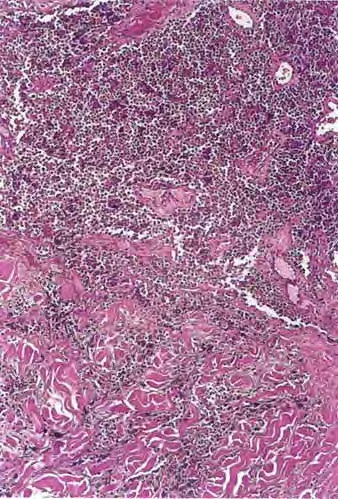

metastasis